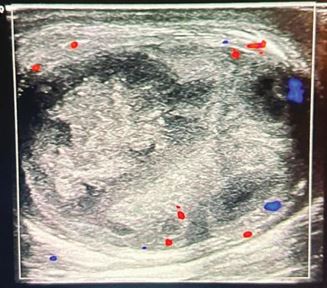

As the clinical signs persisted, the patient came to our clinic with right-sided testicular pain associated with dysuria and fever. The examination found an inflamed and hard right testicle. He had a high C-reactive protein level (192 mg/l) and total with cell count (13,4 x 10^9 / L). The patient underwent a scrotal doppler ultrasound, which revealed:

-Intra-scrotal testicle, enlarged in size, with regular contours, heterogeneous echo structure consisting of well- defined confluent hypoechoic areas, non-vascularized on Doppler, covering the entire testicle measuring 30x45x48 mm. (Figure 1).

Figure 1 Doppler-Ultrasound showing the confluent hypoechoic areas, non-vascularized. -Swollen and heterogeneous epididymis measuring 20 mm.